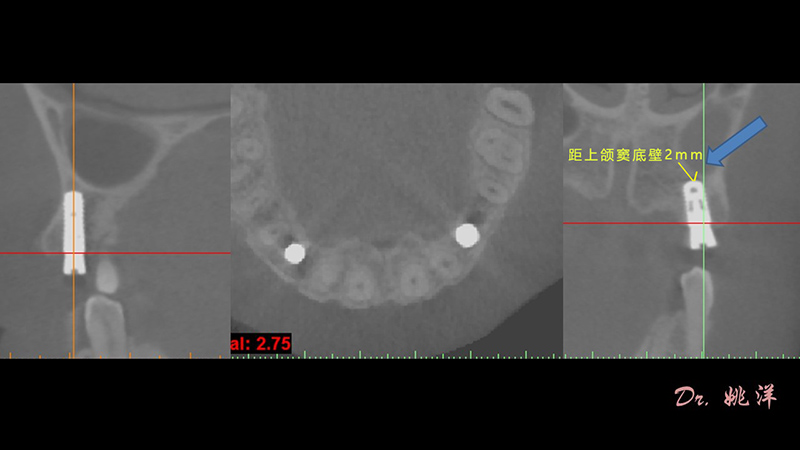

觀察患者CT,可看出患者有上頜竇粘膜囊腫,粘膜囊腫為竇內(nèi)腺體阻塞所致,視情況可有手術(shù)摘除和不予處理兩種方法,此次患者拒絕手術(shù)摘除,故需規(guī)避上頜竇位置。

根據(jù)患者CT顯示,使用種植導(dǎo)航軟件設(shè)術(shù)前手術(shù)方案??紤]到患者拒絕手術(shù)摘除上頜竇囊腫等因素,此次手術(shù)選用了Straumann骨水平4.10*8.0mm的植體,植體末端位點(diǎn)設(shè)計(jì)距上頜竇底壁2mm處的同時(shí)兼顧種植方向和修復(fù)間隙,來(lái)達(dá)到理想的效果。

導(dǎo)航下精細(xì)分配修復(fù)間隙,精細(xì)規(guī)劃植入方向,避開(kāi)上頜竇底,精確植入

從術(shù)后CBCT顯示可以看出,手術(shù)操作中完美地避開(kāi)上頜竇底,并兼顧了正確的種植方向和修復(fù)間隙